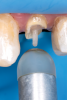

Fig 15. Flowable resin composite injected into the post channel using an angled tip.

Figure 15

The preselected fiber-reinforced composite post was placed into the channel space, and the coronal height was measured and marked (Figure 12). The post was cleaned with alcohol, and its surface was silanated with a ceramic primer and air-dried after 60 seconds. The prepared channel was cleaned with a 2% chlorhexidine solution, rinsed, and dried with an endodontic paper point. The prepared endodontic channel was then etched for 15 seconds with 37.5% phosphoric acid semigel. The gel was agitated in the post channel with a paper point (Figure 13), rinsed for 5 seconds, and dried with an endodontic paper point without dehydrating the dentin structure. A universal adhesive was applied with an applicator brush onto the walls and base of the channel and air-dried (Figure 14); any excess adhesive was absorbed with an endodontic paper point using a rapid intermittent movement. The adhesive was lightly air-thinned using a warm air tooth dryer and light-cured for 40 seconds. An injectable flowable universal resin composite was injected into the post channel using an angled tip (Figure 15). It is important to remove the tip slowly while injecting to prevent the incorporation of air bubbles. The aforementioned fiber post was immediately inserted into the post space to the base of the prepared channel, and light-curing was performed from different positions (ie, coronal, facial, and lingual) for 2 minutes (Figure 16).